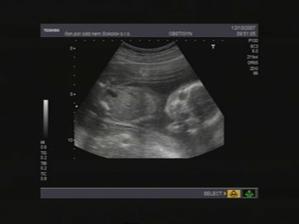

17.8.2007, 12+2tt - I.UTZ - v děloze 1 plod, BPD- 21(12+1), CRL- 59(12+3), srdce se jeví 4 loc, placenta- dors., NT- 1,5.

12.10.2007, 20+2tt - II.UTZ - BPD - 52(21+1), FL - 33(20+5),pravá pánvička 6mm, sonoanatom. norm., srdce- 4 loc xvcr

2.1.2008, 32+0tt- III.UTZ - BPD - 84(32+6), FL - 57(30+3), norm. fem, srdce 4 loc xvcr.